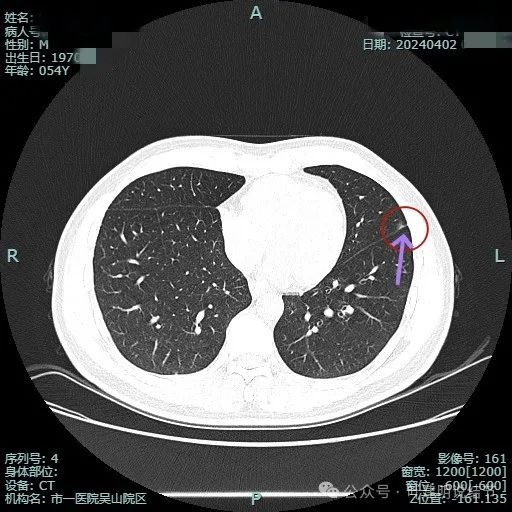

2024年4月复查影像:

病灶大小没有什么变化,当然也没有吸收好转。

病灶连续略显毛刺感。

关键是上图层面怎么贴着叶间裂这侧密度有增高了?偏实性成分!2023年3月时是靶重建情况下都没有见到偏实性成分的。